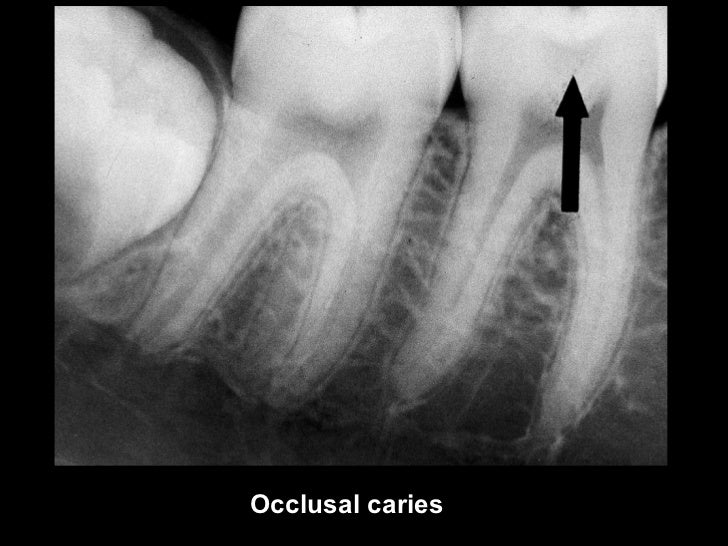

Dental caries Radiology Case